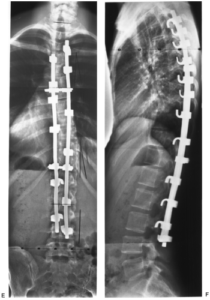

- Транспедикулярная фиксация – эта тактика подразумевает установку в смежные тела позвонков через педикулу (ножки) корригирующей металлоконструкции, представляющей собой винты, которые жестко соединяются между собой специальными штангами. Назначаются подобные манипуляции при переломах и смещениях позвонков, выраженных прогрессирующих сколиозах и стенозах позвоночника.

Транспедикулярная фиксация при сколиозе.